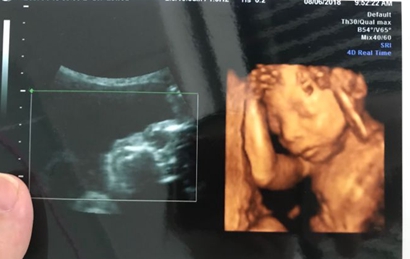

网上流传着四维彩超的报告上如果是有三条线就是女孩,而如果没有三条就是男孩,那么四维女宝宝三条线特征图片长什么样呢,四维男宝也有三条线吗?更多关于生男生女的相关内容尽在孕宝网。

四维女宝宝三条线特征图片长什么样?

其实网上流传着的这种说法并没有依据,原因是网上说的三条线是指女孩生殖器上的线,但是四维彩超上面一般医生是不会显示出完整的生殖器的,还有就是,四维彩超的三条线是无法看出男女性别的,这三条线代表的是脊柱线,还有就是通过三条线来看男女性别的方式误差也是比较大的。

四维彩超其实是实时的三维,是有一个立体成像的过程,因为胎儿是团抱式的,胎儿一部分会被遮挡,所以四维应该会更准确一些,但是不是绝对的。实际在B超进行胎儿性别鉴定时,有可能男孩生殖器被遮挡导致误认为是女孩,因此还是要找专业的医生来看才能下结论。